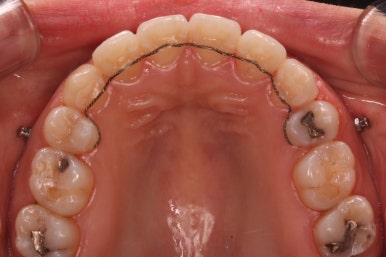

윗니를 봐도 미세하게 남았던 발치를 했던 공간이 없어졌습니다.

마무리 후에 다시 벌어질 수 있는 틈을 유지장치를 붙여 놓았습니다.

아랫니 모습입니다.

남아있는 발치의 공간이 없어졌으며 큰 이동이 없이 마무리가 되었습니다. 안쪽에는 발치공간이 다시 벌어지지 않도록 유지철사를 길게 연장해서 붙였습니다.